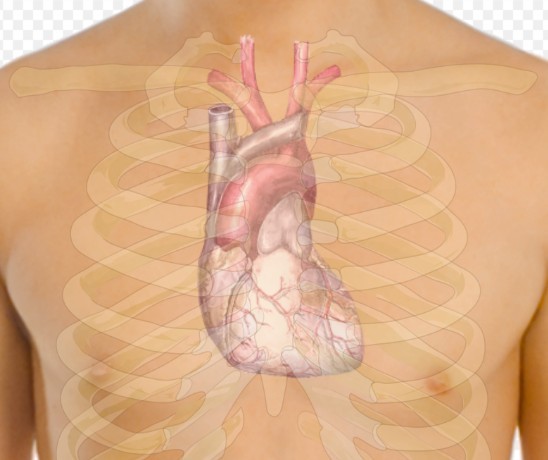

Врач-диетолог Ольга Редина отметила, что употребление кофе и энергетических напитков, содержащих кофеин, может увеличить активность сердца и вызвать изменения в его работе. Алкоголь также считается опасным, особенно при частом и избыточном потреблении, что может нарушить сердечный ритм. Диетолог также указала на возможность вызова аритмии шоколадом у людей с уже имеющимися сердечными заболеваниями.

Она подчеркнула, что пища, богатая жирами и специями, может привести к раздражению нервных окончаний и развитию аритмии. Особенно важно избегать чрезмерного употребления сладкой и соленой пищи, что увеличивает нагрузку на сердце.

Редина рекомендует обследование и коррекцию пищевых привычек для предотвращения серьезных патологий сердца у людей, страдающих от учащенного сердцебиения после употребления определенных продуктов, сообщает Вечерняя Москва.